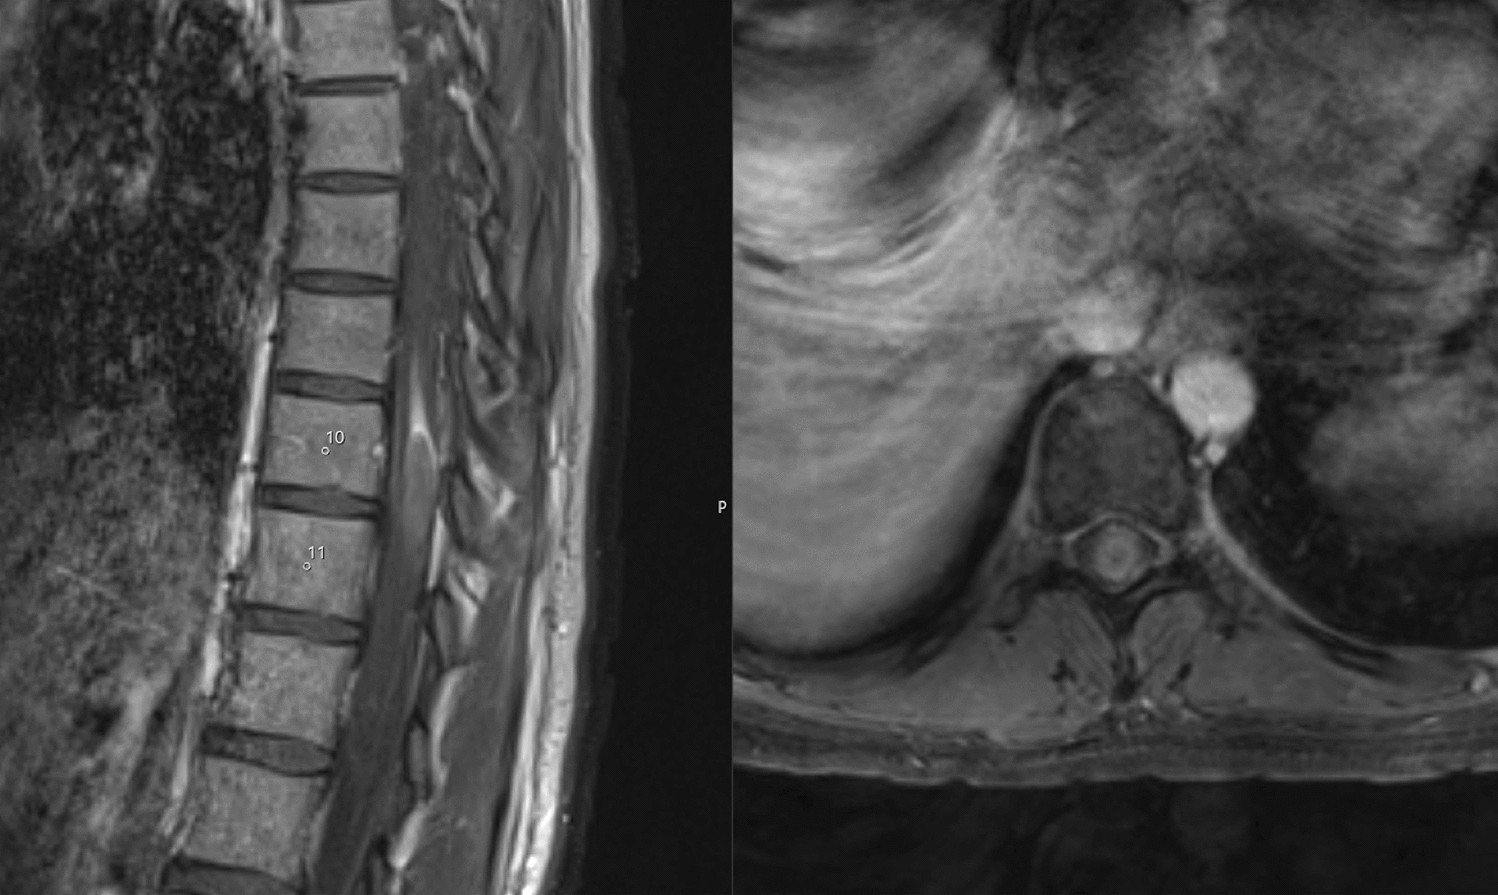

Fig. 2

MR imaging of the thoracic spine with sagittal (left) and axial (right) sequencing and contrast enhancement revealing an intramedullary tumor at the level Th10/Th11